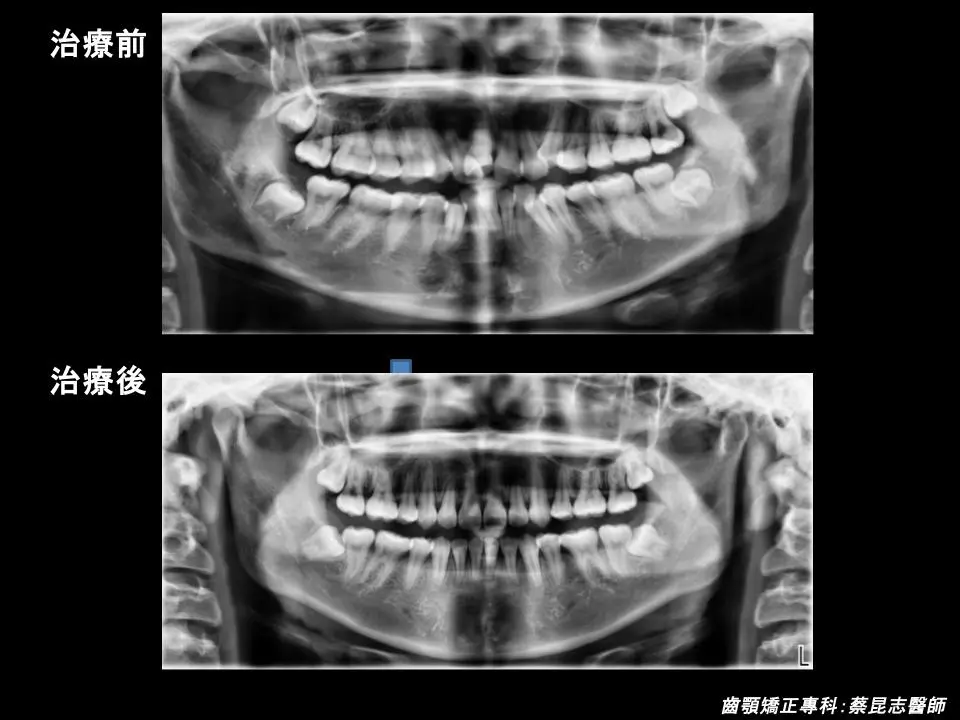

治療前可以見到因為上下顎前牙嚴重擁擠、上顎高位犬齒,造成笑容的不美觀。

又因為上顎前牙過於外暴、上下顎前牙水平距離差距過大,所以側面輪廓上唇過於外凸,和咬合不正。

治療計畫是拔除上、下顎左右兩側各一顆第一小臼齒,讓嚴重擁擠上下顎前牙,有空間可以排列整齊。

將上、下顎前牙後縮,恢復上下顎前牙正常咬合,並改善側臉輪廓上唇過於外凸的外觀,凸顯側臉下巴輪廓。